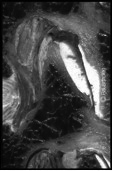

Die weitaus meisten Rückenprobleme sind duch einen relativ früh beginnenden Verschleissprozess der Wirbelsäule bedingt.